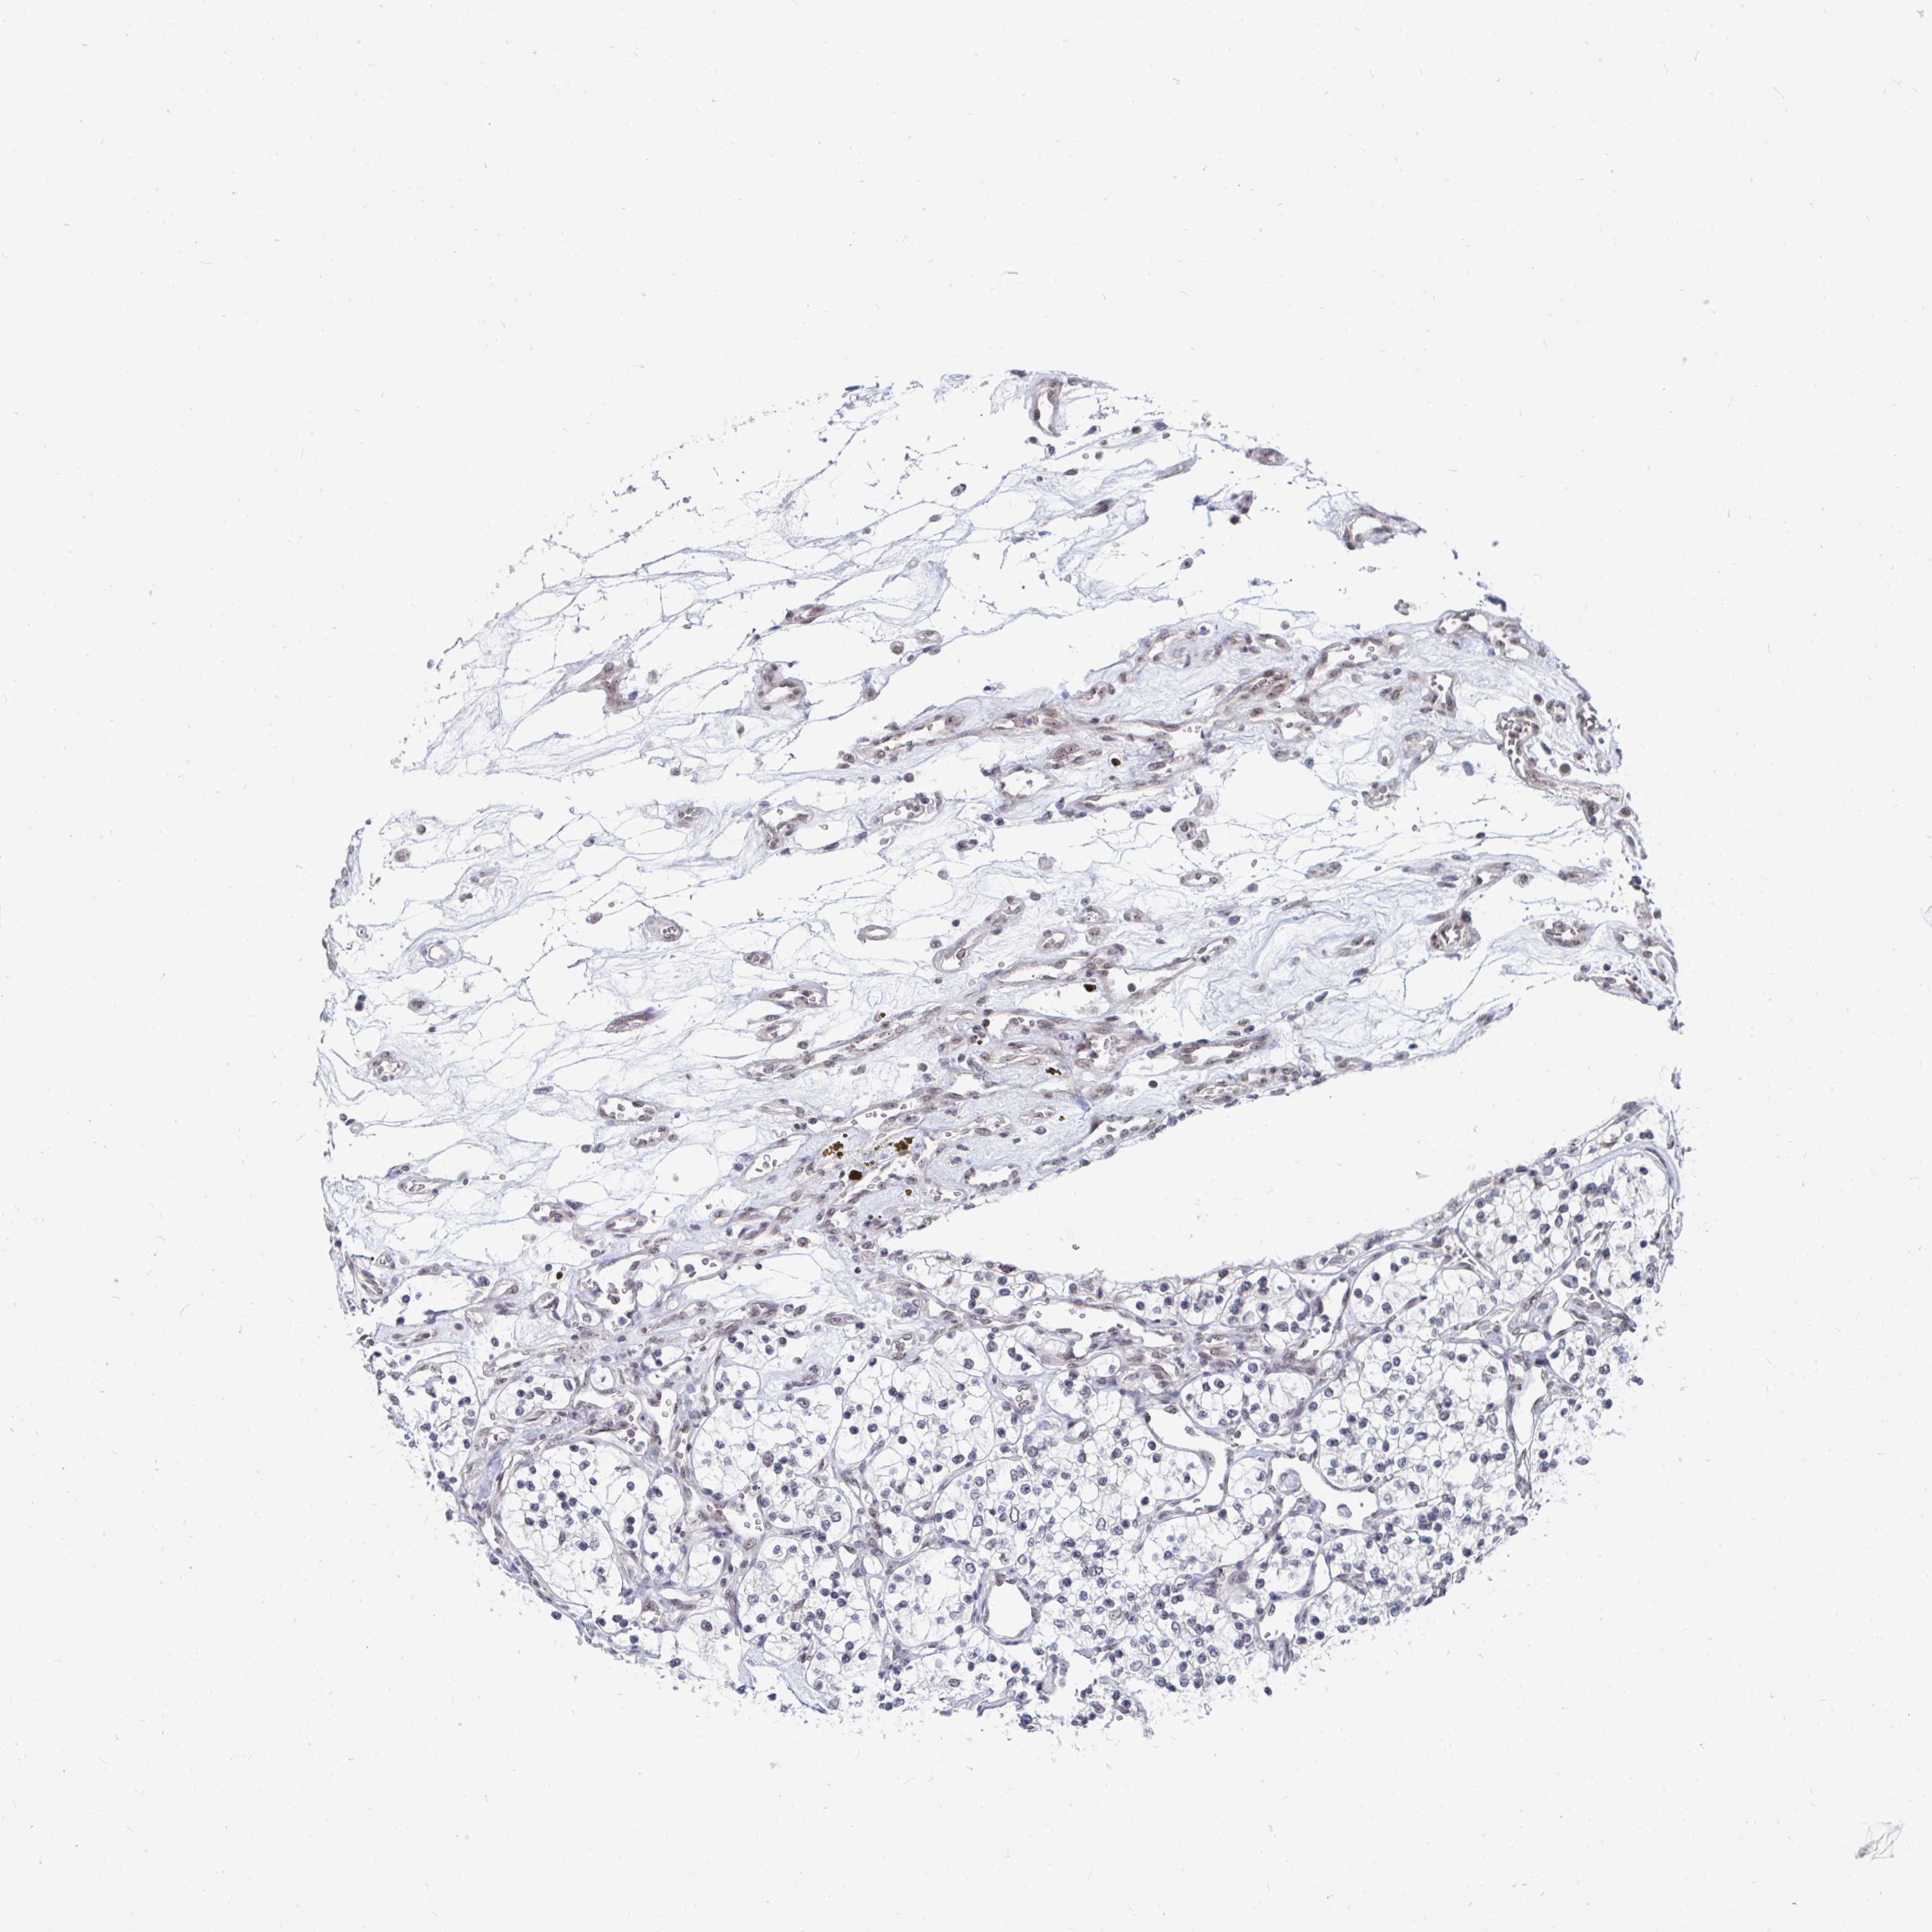

KIDNEY RENAL CLEAR CELL CARCINOMA (VALIDATION) - Interactive survival scatter ploti

The Survival Scatter plot shows the clinical status (i.e. dead or alive) for all individuals in the patient cohort, based on the same data that underlies the corresponding Kaplan-Meier plots. Patients that are alive at last time for follow-up are shown in blue and patients who have died during the study are shown in red.

The x-axis shows the expression levels (FPKM) of the investigated gene in the tumor tissue at the time of diagnosis. The y-axis shows the follow-up time after diagnosis (years). Both axes are complimented with kernel density curves demonstrating the data density over the axes. The top density plot shows the expression levels (FPKM) distribution among dead (red) and alive patients (blue). The right density plot shows the data density of the survived years of dead patients with high and low expression levels respectively, stratified using the cutoff indicated by the vertical dashed line through the Survival Scatter plot. This cutoff is automatically defined based on the FPKM cutoff that minimizes the p-score. The cutoff can be changed by dragging the vertical line or by entering a cutoff value in the square labeled "Current cut-off".

Under the Survival Scatter plot the p-score landscape (black curve; left axis) is shown together with dead median separation (red curve; right axis). Dead median separation is the difference in median mRNA expression between patients who have died with high and low expression, respectively. It is calculated as follows: median FPKM expression of dead patients with high expression - median FPKM expression of dead patients with low expression. This is intended to aid the user in visually exploring custom cutoffs and the associated p-scores and dead median separation.

Individual patient data is displayed and can be filtered by clicking on one or more of the category buttons on the top of the page. Categories describing expression level and patient information include: high, low, alive, dead, female, male and tumor stages. The scale of the x-axis can be toggled between linear and log-scale by clicking on the "x log" button. Mouse-over function shows TCGA ID, patient information and mRNA expression (FPKM) for each patient.

& Survival analysisi

Kaplan-Meier plots summarize results from analysis of correlation between mRNA expression level and patient survival. Patients were divided based on level of expression into one of the two groups "low" (under cut off) or "high" (over cut off). X-axis shows time for survival (years) and y-axis shows the probability of survival, where 1.0 corresponds to 100 percent.

TRIP12 is not prognostic in Kidney Renal Clear Cell Carcinoma (validation)

Best expression cut offi

Based on the FPKM value of each gene, patients were classified into two groups and association between prognosis (survival) and gene expression (FPKM) was examined. The best expression cut-off refers the FPKM value that yields maximal difference with regard to survival between the two groups at the lowest log-rank P-value. Best expression cut-off was selected based on survival analysis .

When clicking on this number, the vertical dashed line indicating cut-off, the interactive survival plot, and the Kaplan-Meier curve will be adjusted to show results based on the best expression cut-off.

: 77.98

Median expressioni

Median expression refers to the median FPKM value calculated based on the gene expression (FPKM) data from all patients in this dataset. When clicking on this number, the vertical dashed line indicating cut-off, the interactive survival plot, and the Kaplan-Meier curve will be adjusted to show results based on the median expression.

: N/A

Median follow up timei

Median follow up time refers to the median time (years) after diagnosis with this type of cancer, based on clinical data from all patients in this dataset.

P scorei

Log-rank P value for Kaplan-Meier plot showing results from analysis of correlation between mRNA expression level and patient survival.

N/A

5-year survival highi

5-year survival for patients with higher expression than the expression cutoff.

For melanoma and glioma, 3-year survival is shown.

5-year survival lowi

5-year survival for patients with lower expression than the expression cutoff.

TCGA RNA samplesi

RNA-seq data is reported as average FPKM (number Fragments Per Kilobase of exon per Million reads), generated by the The Cancer Genome Atlas (TCGA) .

Normal distribution across the dataset is visualized with box plots, shown as median and 25th and 75th percentiles. Points are displayed as outliers if they are above or below 1.5 times the interquartile range. FPKM values of the individual samples are presented next to the box plot.

Average pTPM 62.1

Number of samples 100